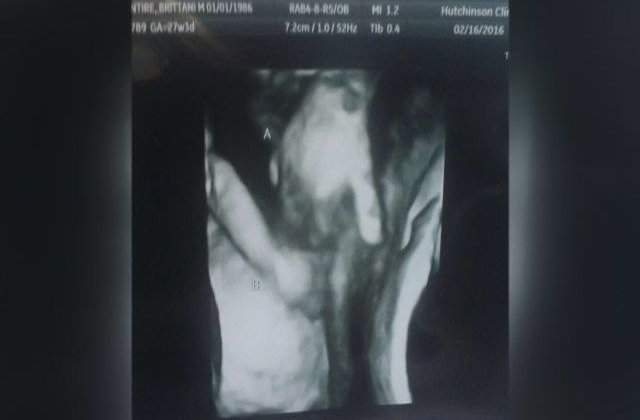

Un făt cu probleme de sănătate a fost surprins la ecograf în timp ce strângea în uter mâna surorii sale gemene.

Răpuși de veste, părinții au avut parte de un moment emoționant la ecograf când au văzut cum băiețelul lor, deși insuficient dezvoltat și de patru ori mai mic decât celălalt făt, o ținea strâns de mână pe sora lui.

"Cei mai mulți gemeni se hârjonesc, se lovesc unul pe celălalt, când medicul încearcă să îi prindă în poză, dar acum se pare că sora era foarte protectoare cu fratele ei”, a mai spus mama celor doi micuți. "Sora lui, Madilyn, este singura care poate să fie în mod real acolo, lângă el, şi care îi poate oferi sprijin, aşa că ne linişteşte gândul că, dacă va muri, nu va fi singur”, a adăugat aceasta pentru postul de televiziune local KWCH.